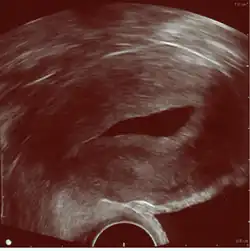

Left hydrosalpinx on gynecologic ultrasonography